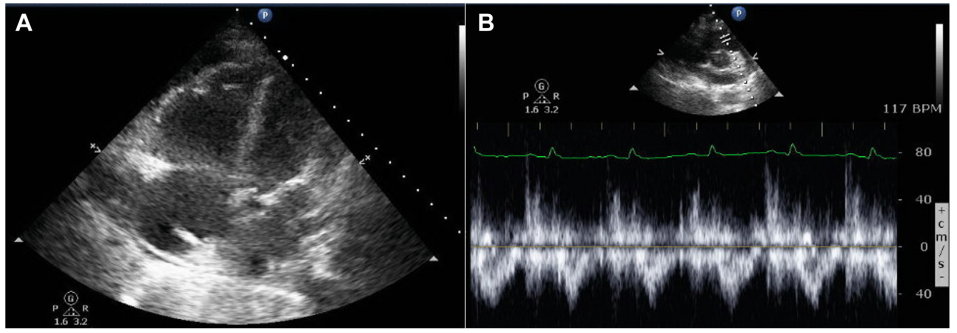

图片图2 入院时TTE检查

注:入院时TTE显示(A)心尖四腔切面可见右心房和心室中度扩张,(B)右室流出道收缩中期切迹(箭头所示),符合毛细血管前性肺动脉高压表现。此时患者正在接受吸入NO(5 PPM)和西地那非(20 mg,每8小时1次)治疗。